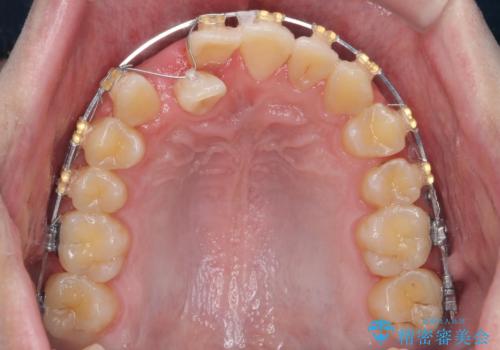

正中過剰埋伏歯で生じた前歯の審美障害 矯正治療での改善

- 前歯の見た目に悩まれて来院されました。

当初他院では、抜歯を行いセラミックブリッジを提案されていましたが、他の方法はないかと総合歯科治療を行う当院へと相談来院されました。

「時間がかかっても良いので、できれば歯を抜かずに矯正治療で治したい。」という強い希望があったので、矯正治療で歯並び・審美性の改善を計画します。